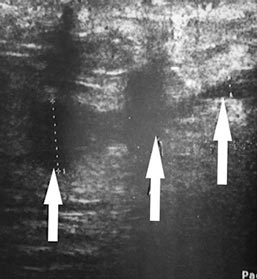

Наглядно ультразвуковая картина послеоперационных ран представлена на рис. 1–5. Показана положительная динамика разрешения полостных образований послеоперационной раны на 3-и, 5-е и 7-е сутки. Переход гипоэхогенной зоны в сторону уменьшения и появления участков гиперэхогенной структуры на 7-е сутки послеоперационного периода свидетельствует об уменьшении воспалительных процессов, снижении риска увеличения полостных образований и формировании фазы регенерации.

Рис. 3. Ультразвуковая картина передней брюшной стенки живота пациента Б. 52 лет на 3-и сутки после лапаротомии. Гипоэхогенная зона в области апоневроза белой линии живота составляет 11,7 мм

Рис. 4. Ультразвуковая картина передней брюшной стенки живота того же больного (см. рис. 3) на 5-е сутки после лапаротомии. Гипоэхогенная зона в области апоневроза белой линии живота уменьшилась до 5,7 мм